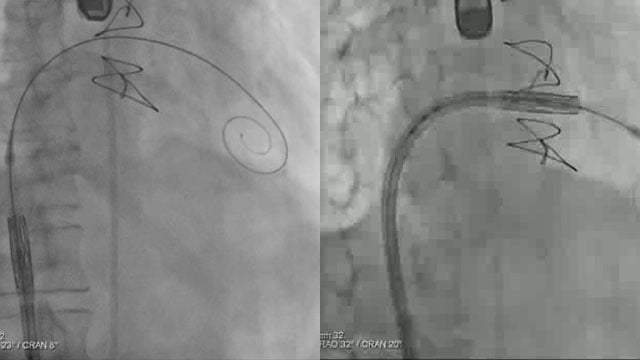

A simple maneuver to track the wire during a transseptal mitral valve-in-valve procedure

Advancing a transcatheter heart valve through the septostomy can be tricky, with the wire sometimes prolapsing into the left atrium.

This step-by-step tutorial demonstrates a simple yet effective maneuver that allows smooth, controlled navigation from the right atrium to the mitral position, ensuring precise valve deployment.